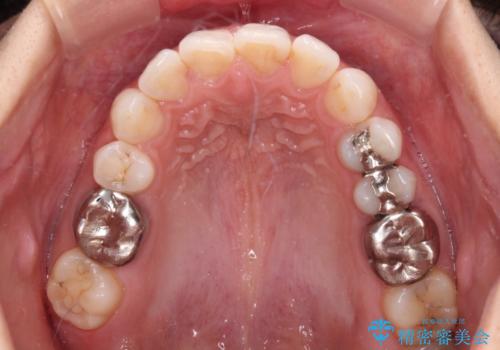

- 奥歯の銀歯が外れたことをきっかけに、全ての銀歯をセラミックに替えたいとのことで来院された患者様です。

第一大臼歯4本と、メタルインレーが装着されている2歯をセラミッククラウンならびにセラミックインレーにて補綴治療・修復治療を行うこととしました。

口腔内から、土台も含め銀歯がなくなったことでメタルフリーとなりました。